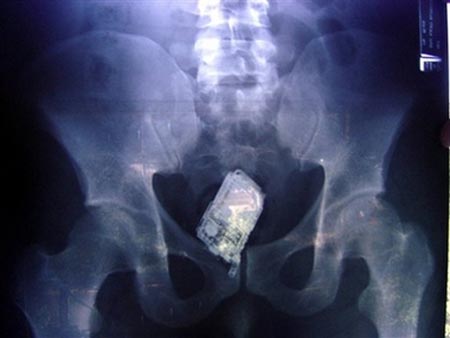

โทรศัพท์มือถือ